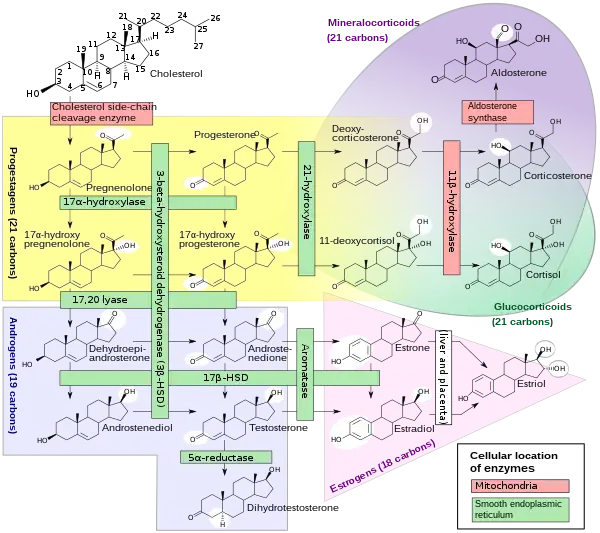

Its cells develop from the follicular cells surrounding the ovarian follicle.[5] The follicular theca cells luteinize into small luteal cells (thecal-lutein cells) and follicular granulosa cells luteinize into large luteal cells (granulosal-lutein cells) forming the corpus luteum. Progesterone is synthesized from cholesterol by both the large and small luteal cells upon luteal maturation. Cholesterol-LDL complexes bind to receptors on the plasma membrane of luteal cells and are internalized. Cholesterol is released and stored within the cell as cholesterol ester. LDL is recycled for further cholesterol transport. Large luteal cells produce more progesterone due to uninhibited/basal levels of protein kinase A (PKA) activity within the cell. Small luteal cells have LH receptors that regulate PKA activity within the cell. PKA actively phosphorylates steroidogenic acute regulatory protein (StAR) and translocator protein to transport cholesterol from the outer mitochondrial membrane to the inner mitochondrial membrane.[6]

The development of the corpus luteum is accompanied by an increase in the level of the steroidogenic enzyme P450scc that converts cholesterol to pregnenolone in the mitochondria.[7] Pregnenolone is then converted to progesterone that is secreted out of the cell and into the blood stream. During the bovine estrous cycle, plasma levels of progesterone increase in parallel to the levels of P450scc and its electron donor adrenodoxin, indicating that progesterone secretion is a result of enhanced expression of P450scc in the corpus luteum.[7]

Like the previous theca cells, the theca lutein cells lack the aromatase enzyme that is necessary to produce estrogen, so they can only perform steroidogenesis until formation of androgens. The granulosa lutein cells do have aromatase, and use it to produce estrogens, using the androgens previously synthesized by the theca lutein cells, as the granulosa lutein cells in themselves do not have the 17α-hydroxylase or 17,20 lyase to produce androgens.[5] Once the corpus luteum regresses the remnant is known as corpus albicans.[12]